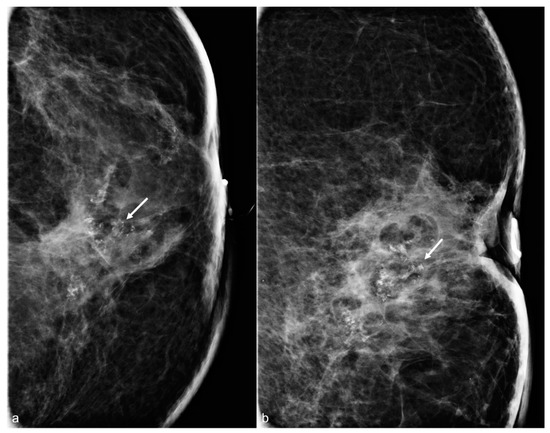

Figure 4. A 65-year-old woman with a history of subglandular silicone implants. Mammograms with magnified CC (a) and ML (b) views demonstrate calcified (arrows) and non-calcified fat necrosis in the left central breast. The patient underwent BES four years earlier.